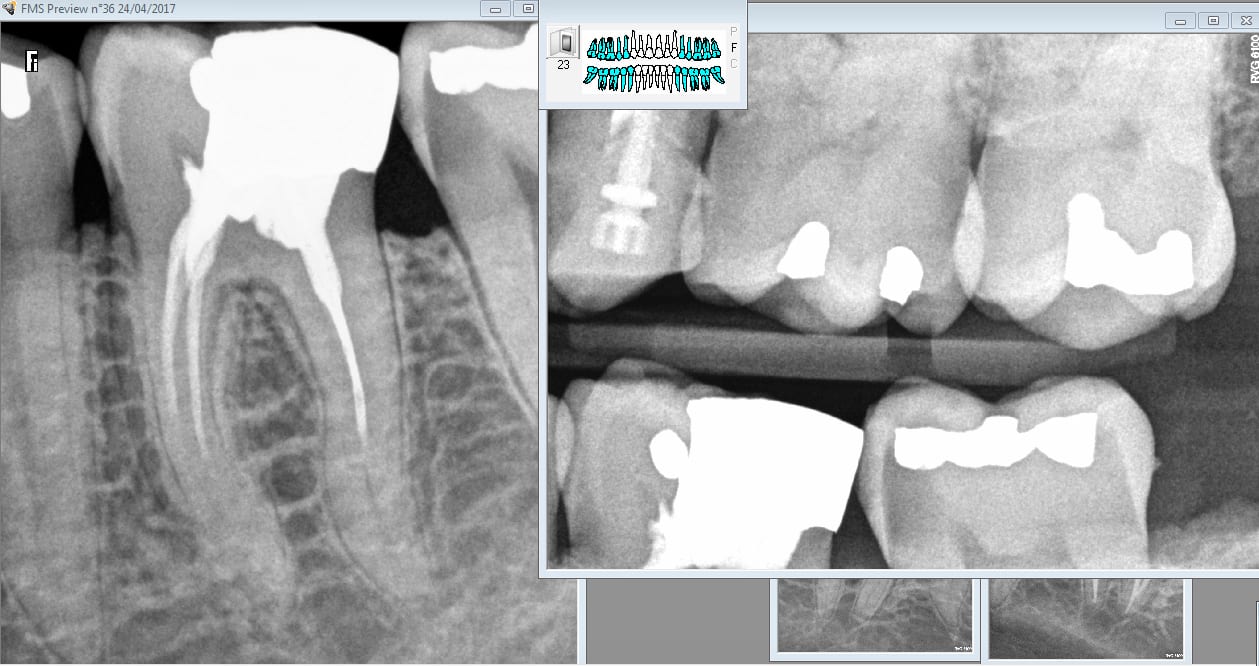

Alleeeez je peux pas résister. Nouveau patient bilan radio + endo 46 ( pas mal pour un premier RDV de 30 minutes). Bon j'avoue j'ai débordé de 10 mn.

Tiens casa a fait l'endo de 36 ? Pas de couronne dessus c'est tout à ton honneur. -)

Tu vois par exemple casa n'aurait pas soigné cette 37 juste derrière le merveilleux traitement endo de 36. parce que casa n'aurait pas fait de rétro coronaire. Que va il se passer endo ou pas ? A vrai dire j'en sais rien tout dépend de si effraction pulpaire ou pas lors du nettoyage de la cavité ca a l'air limite. -)